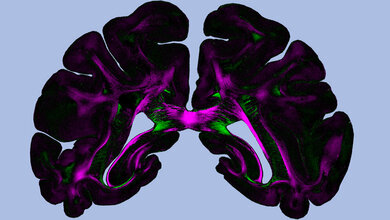

Ein Team des Lehrstuhls Zellphysiologie der Ruhr-Universität Bochum (RUB) um Prof. Dr. Dietmar Fischer hat neue Mechanismen entschlüsselt, die die Regeneration von Nervenfasern ermöglicht. Das könnte neue Therapieansätze bei Hirn-, Sehnerv- und Rückenmarksverletzungen eröffnen. Gehirn, Rückenmark und Sehnerven werden unter dem Begriff Zentrales Nervensystem (ZNS) zusammengefasst. Die Nervenfasern, sogenannte Axone, können nach Verletzung nicht mehr nachwachsen, sodass Schäden dauerhaft sind. „Man kann die Regenerationsfähigkeit von Nervenzellen des Zentralen Nervensystems zum Teil wiederherstellen, indem man das hemmende Protein PTEN eliminiert“, erklärt Dietmar Fischer. „Allerdings löst ein solcher sogenannter Knockout viele unterschiedliche Reaktionen in den Zellen gleichzeitig aus, die auch häufig zu Krebs führen.“ Die direkte Hemmung dieses Proteins ist deshalb für therapeutische Ansätze beim Menschen ungeeignet. Außerdem ließ sich der ursprünglich postulierte Mechanismus, der der erneuten Regenerationsfähigkeit nach PTEN-Knockout zugrunde liegt, nicht durch weiterführende Studien bestätigen, sodass die Forscher nach alternativen Erklärungen suchten.